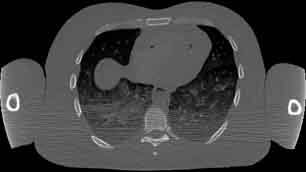

Visible Human male: Sectio transversalis 1458

CT

NMR

Pd                          / T2 \                         T1